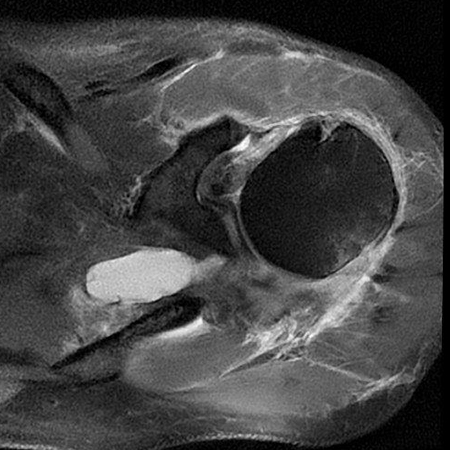

Rotatorenmanschettenriß in der Kernspintomographie

ROTATORENMANSCHETTENMASSENRUPTUR

Rotatorenmanschettemassenruptur: Subscapularis- und Infraspinatus-Abriss

Rotatorenmanschettemassenruptur: Supraspinatusabriss

Der Patient berichtet, dass er beim Volleyballspiel beim Überkopfaufschlag eine Schultergelenksverrenkung (Luxation) erlitten habe. Er habe bereits zuvor leichte Beschwerden gehabt. In der Kernspintomographie zeigte sich ein Sehnenabriss an der Supraspinatussehne wie auch eine Kapselverletzung am vorderen unteren Gelenk. Arthroskopisches Vorgehen mit Rekonstruktion der Läsionen. Der Patient demonstriert nach 6 Monaten im Januar 2022 eine stabile Schulter im Rahmen der Liegestütze. Eine Wiederaufnahme des Volleyballspielens ist im Weiteren geplant.

62-jährige Patientin mit erheblichen Schmerzen und vollschichtiger Supraspinatussehnenablösung. Die Sehne war sehr weit zurückgezogen, bereits sichtbar auf der präoperativen Kernspintomographie und ließ sich auch intraoperativ nicht so weit mobilisieren. Eine Rekonstruktion war spannungsarm nicht möglich. Es wurde ein mit Flüssigkeit gefüllter Ballon unter dem Schulterdach arthroskopisch gestützt eingeschoben und entfaltet. Dieser Ballon führt neben einer Abstandshaltung zum Schulterdach zu einer Fremdköperreaktion und Membranbildung. Durch die anhaltende Trainingstherapie konnte die Patientin trotz des Defektes eine Rezentrierung des Gelenkes mit sehr guter anhaltender Funktion erzielen.